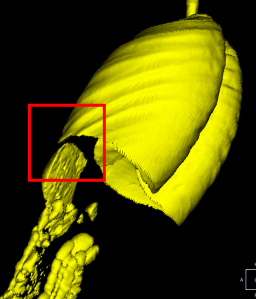

Далее выделим дыхательные органы как максимальный по объему объект. Дыхательные органы — это отдельный объект. Связи между легкими и воздухом внутри желудочно-кишечного тракта нет.

Стоит заметить, что важен правильный выбор порога рентгеновской плотности на начальном шаге порогового преобразования. Иначе в некоторых случаях может не оказаться связи между двумя лёгкими в результате низкого разрешения. Например, если считать, что воксели дыхательных органов имеют рентгеновскую плотность от -500 HU и менее, то в случае, приведённом ниже, выделение дыхательных органов как крупнейшего по объёму объекта приведёт к ошибке, так как отсутствует связь между двумя лёгкими. Поэтому следует повысить порог до -300 HU.